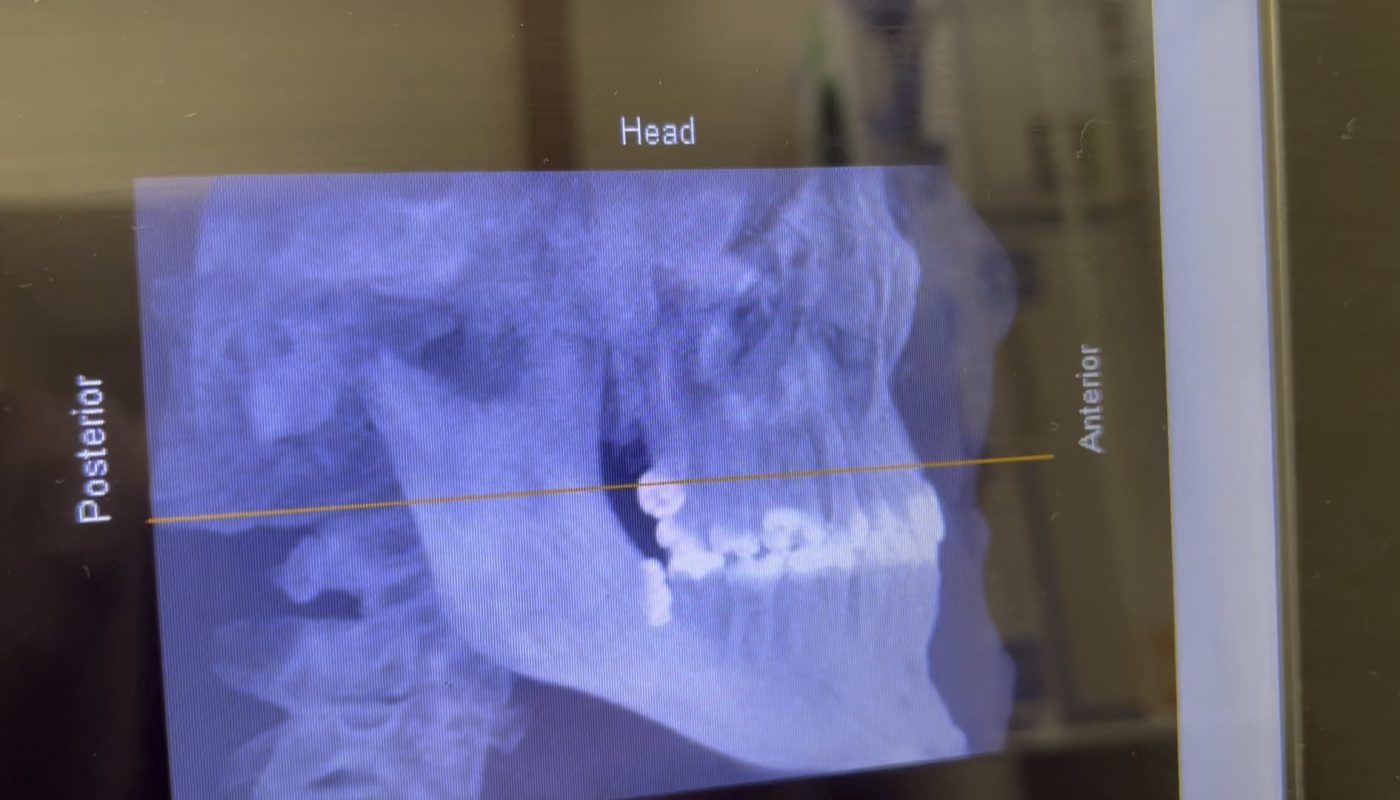

The Xray I just got for my upcoming —second— wisdom tooth extraction surgery

Whether you’re a seasoned wisdom tooth extraction veteran or nervously preparing for your second surgery, one thing remains certain: the X-ray is a critical first step in planning a safe and successful procedure. If you’ve recently had a dental X-ray for your upcoming second wisdom tooth removal, you might wonder what the radiographs reveal and how they guide your oral surgeon. In this article, we’ll break down everything you need to know about your pre-extraction X-ray—from its purpose to what comes next.

Wisdom teeth (third molars) often develop at unpredictable angles, with roots positioned close to nerves, sinuses, or neighboring teeth. Unlike a standard dental exam, an X-ray provides a detailed 3D view of:

• Tooth Positioning: Will your tooth be impacted, horizontal, or fully erupted?

• Root Shape & Depth: Are roots curved, fused, or near critical structures like the inferior alveolar nerve?

• Sinus Proximity: Upper wisdom teeth may extend into sinus cavities.

• Bone Density: This affects extraction complexity, especially with age.

For your second extraction, the X-ray helps identify changes since your first surgery, such as shifting teeth or new complications.